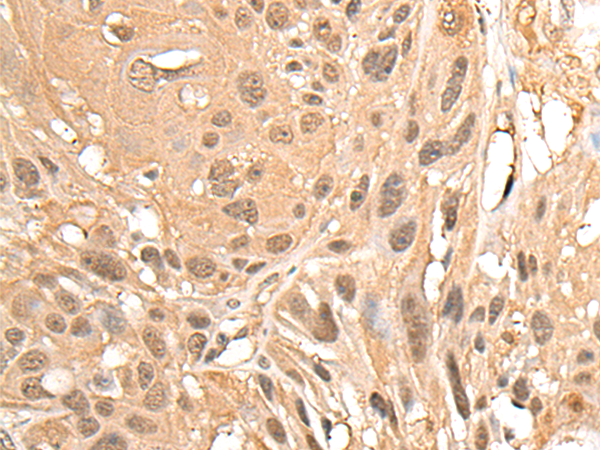

分类: 科研抗体货号: P06321别名: GY2; FKSG1; WDR14; WDVCF; DGCRK3应用: IHC反应种属: Human, Mouse